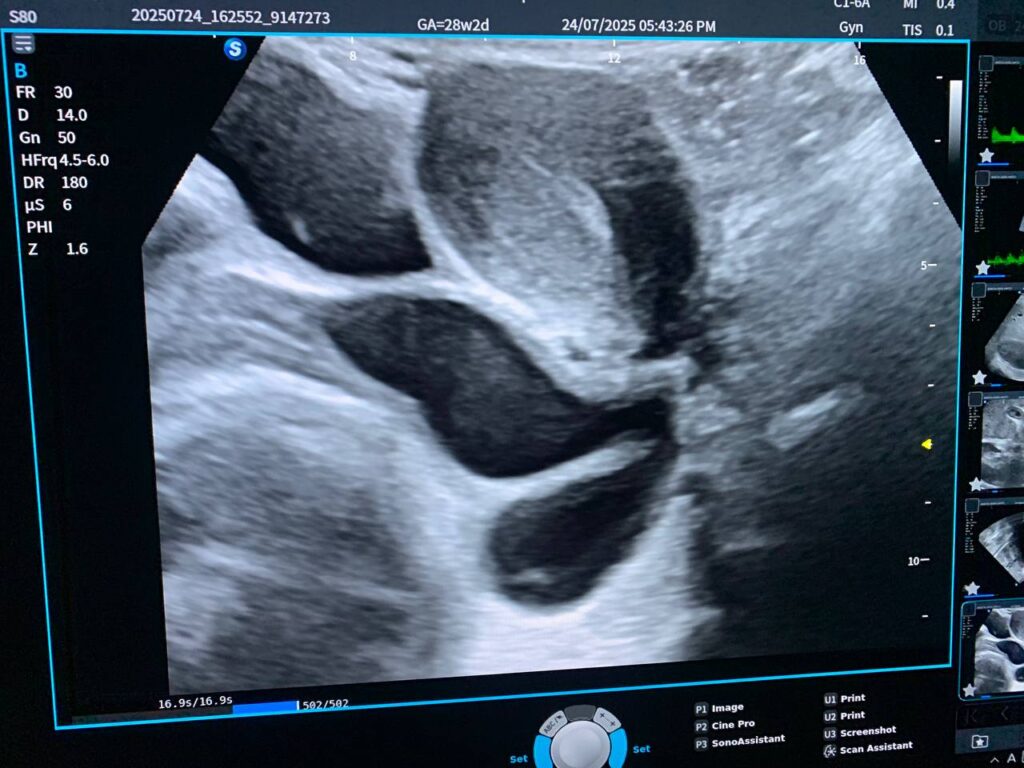

Presence of tortuous cystic mass size about 52x39mm, on the left sided posterior uterus & left vaginal canal , its located of the sacral region , Tarlov cyst cannot be excluded